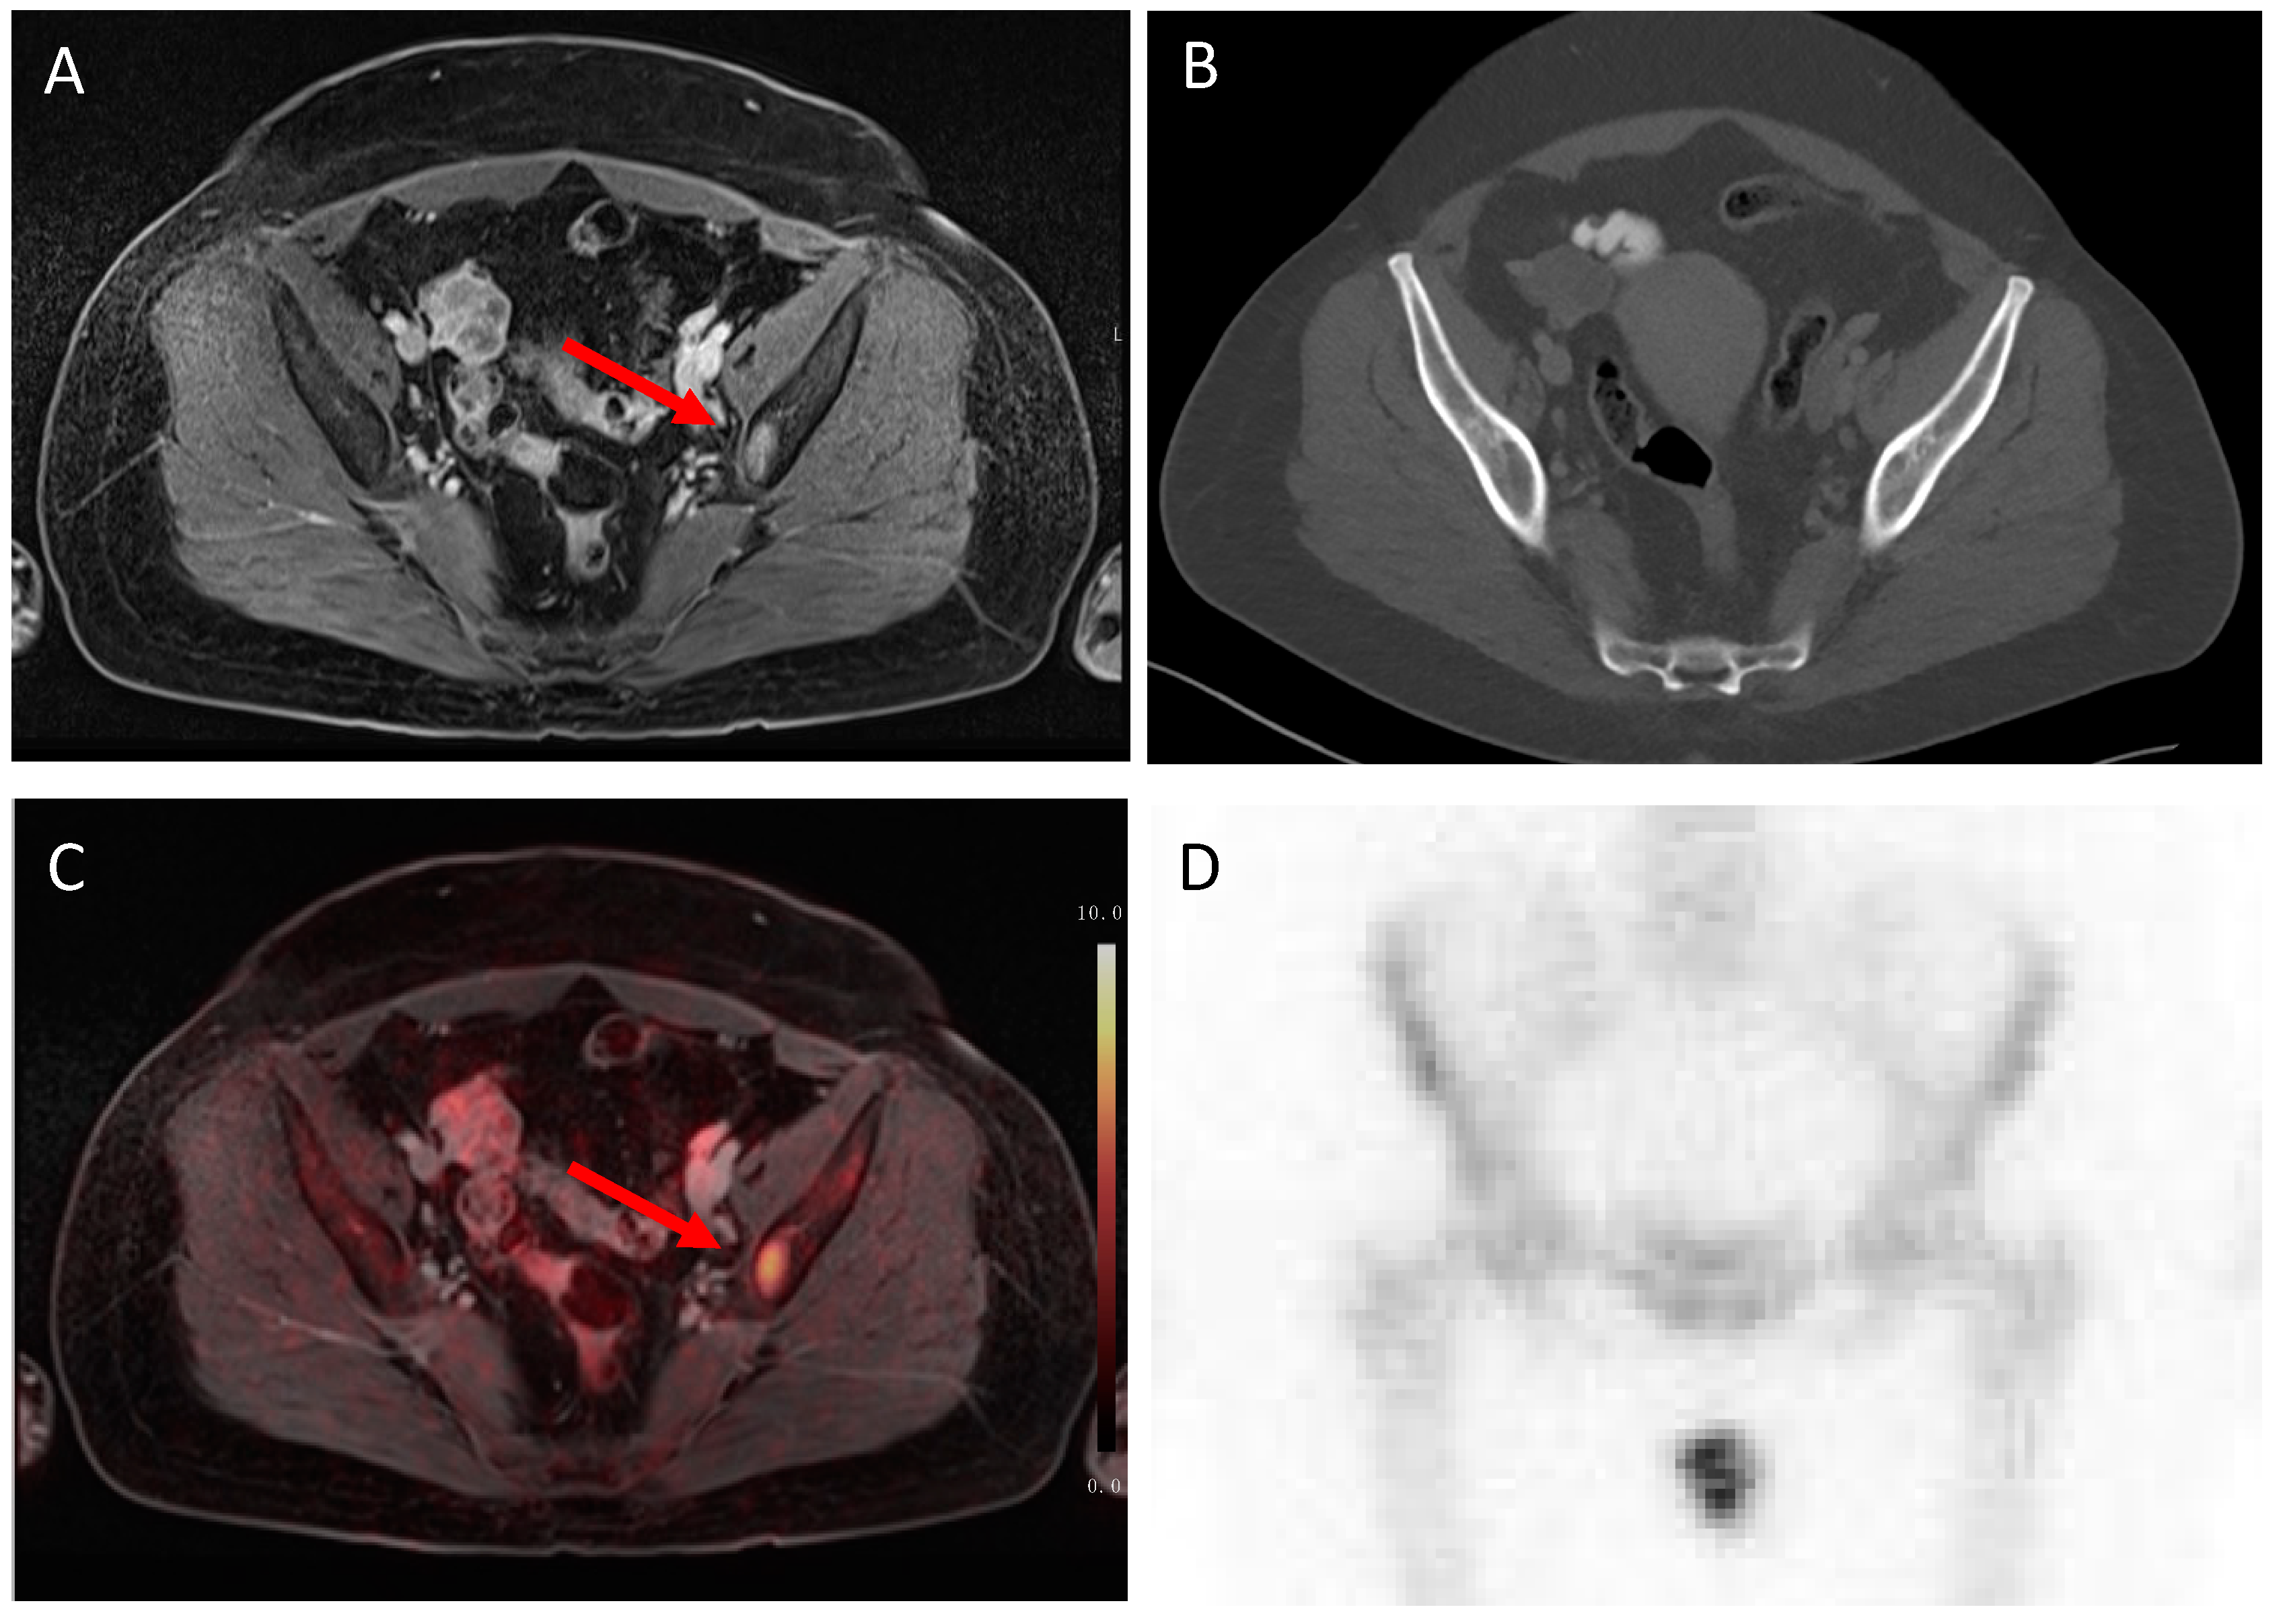

3.2. N Staging

3.3. M Staging